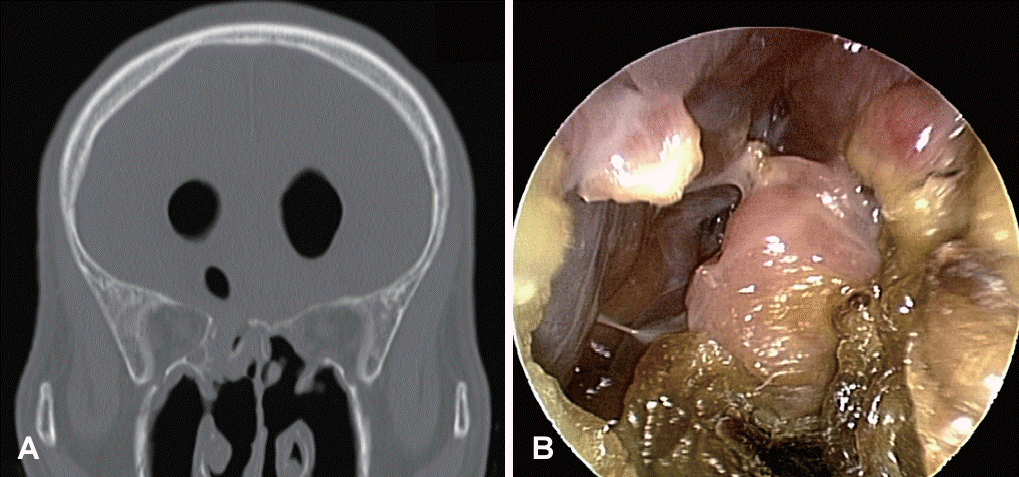

At the previous hospital, endoscopic skull base repair was performed using an ipsilateral septal flap. Although pneumocephalus appeared to decrease immediately after surgery, CSF leakage recurred repeatedly despite of the second and third revision surgeries. Following the last surgery, follow-up CT scan showed the diffuse ventricular dilatation and a skull base defect at the right posterior ethmoid roof (Onodi cell) (Fig. 2A). Therefore, the patient transferred to our center for the reoperation. At the initial visit to our clinic, no overt CSF leakage was evident upon endoscopic examination (Fig. 2B). However, intermittent fever spiking up to 38.3°C and worsening drowsiness in the patient implied the meningitis.

Fig. 2.

Preoperative CT and 0º endoscopic findings. A: Slightly decreased, but still notable amount of pneumoventricle and pneumocephalus compared to initial post traumatic findings. B: Endoscopic examination showed no definite evidence of overt cerebrospinal fluid leakage.